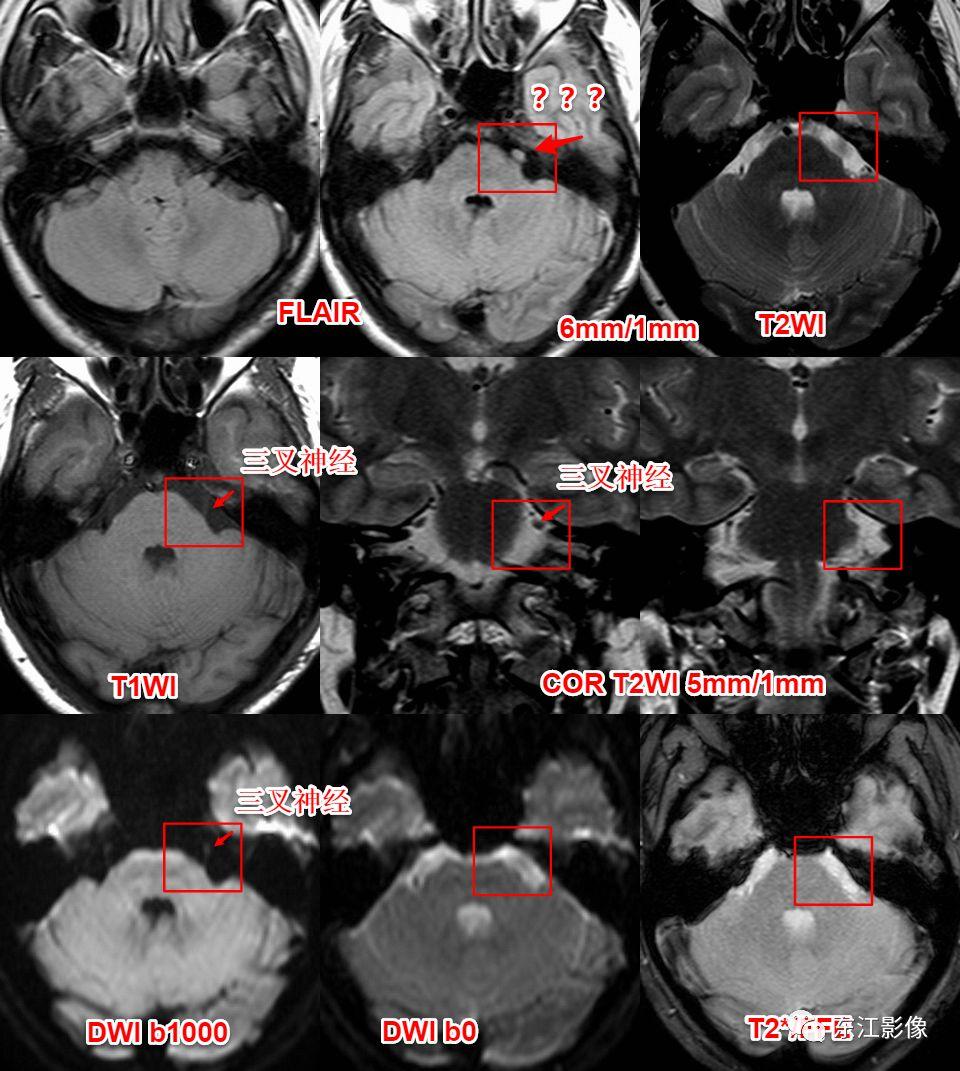

桥前池脑脊液流动伪影。